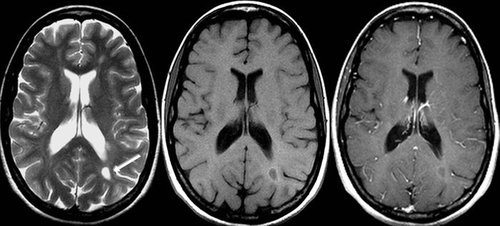

Siempre se nos ha dicho que la sal es dañina, incluso, desde hace varios años los restaurantes han dejado de poner sal en la mesa y únicamente te dan sal extra si la pides. La sal afecta en la retención de líquidos y problemas cardíacos, además, un nuevo estudio señala que el consumo excesivo de sal puede desencadenar un cambio cerebral que conduce a una función cognitiva más baja y, con el tiempo, a la demencia.

El sistema vascular del cerebro depende del óxido nítrico para el flujo sanguíneo y la disminución de la presión arterial. El aumento del consumo de sal puede causar una caída en la cantidad de óxido nítrico en el cuerpo. Lo anterior afecta a una proteína llamada tau. Cuando tau se ve afectada por la gota de óxido nítrico, comienza a acumularse.

Esta acumulación de la proteína tau se relaciona previamente con la enfermedad de Alzheimer y otros problemas cognitivos. De hecho, cuando los investigadores restauraron la producción de óxido nítrico en los ratones, su capacidad cognitiva mejoró. Por otro lado, los ratones criados sin la capacidad de producir proteína tau, o aquellos que fueron tratados con anticuerpos anti-tau, no mostraron deterioro cognitivo.

Todo lo anterior indica que existe una relación causal entre la sal de la dieta, la disfunción de los vasos sanguíneos en el cerebro y los problemas con la producción de tau en el cerebro, por lo cual o ideal es disminuir la ingesta de este ingrediente en nuestras comidas diarias.